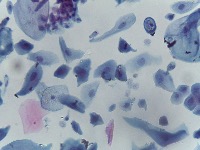

Medical Diagnostics: This model can be used in the healthcare industry to provide high-speed automated analysis of pathology slides, determining whether cells are normal or abnormal, and assisting in diagnosis of various diseases such as cancer.

Scientific Research: Researchers studying cell biology or genetics can use this AI model for their studies on cellular abnormalities and diseases. This can accelerate the onset of breakthroughs in medical science.

Pharmaceutical Applications: Pharmaceutical companies can use this model in drug discovery and development process. By identifying how different medications affect normal and abnormal cells, they can speed up and enhance their research.

Educational Tool: This AI model could serve as a rich educational tool in courses related to biology, medicine and health sciences, helping students to visualize and understand differences between normal and abnormal cells.

Personalized Medicine: This model can be used to analyze patients' cells to create personalized treatment plans. Understanding an individual's cellular structure could help healthcare professionals tailor treatments to the patient's specific needs.